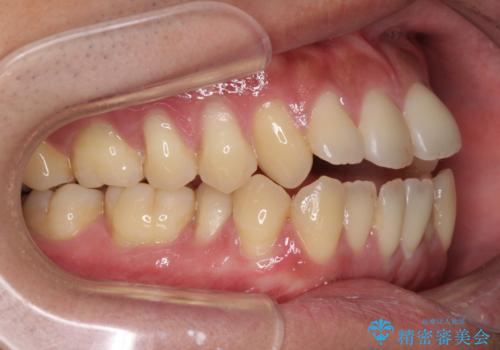

- 上下前歯の隙間と口元の出っ張った感じを気にして来院された患者様です。

上下の隙間は舌突出癖によるもので、またその癖により前歯が前方に出ている状態でした。

口元の出っ張りを改善するため、上下左右第一小臼歯4本を抜去し、ワイヤー装置にて矯正治療を行うこととしました。